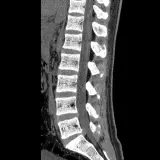

Over 2,100 interactive radiology cases, curated by radiologists for your level of training. Scroll, window, and view cases full screen — just like on PACS. Click linked findings in each writeup to jump straight to them on the image. Cases include sample reports, a focused discussion section, original illustrations, and videos.

完全交互式病例,配备您在 PACS 上期待的各项工具——滚动、调窗、缩放、平移、测量、ROI 和全屏模式。

丰富的标注直接在病例图像上突出关键发现。点击病例讲解中的关联发现,即可跳转至其在扫描上的精确位置。